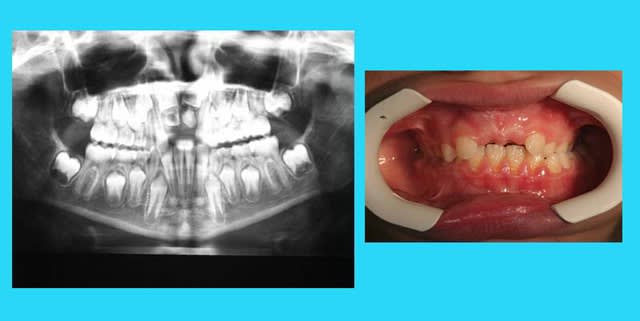

Jeune garcon de 6 ans,2 mois présentant une 52 et une 12 surnumeraire.Vu son retard dentaire,pensez vous qu'il est préferable de pratiquer l'extraction de la 52 mésiale maintenant ou de laisser évoluer et revoir ce jeune patient dans 6 mois;

le gros souci c'est ta 11 d'après ce que je constate est placée au niveau du seuil narinaire à cause de la 12 bis et par voie de conséquence la 52.

En principe il faut lever l'obstacle pour espérer une reprise des phénomènes de dentition.

Fait voir quelle est la bonne dent à extraire selon l'imagerie 3D, voir laquelle est la plus dysmorphique des 12.

Perso je dégage 52 et 12bis, je laisse évoluer 6 mois pour surveiller la 11 sinon faudra aussi la coller pour la tracter à terme.

Merci pour les réponses.L'ortho me demande d'extraire la 52 mais à ce stade ,je ne comprend pas trop l'intéret.

J'envisageais ,à mon sens, d'attendre encore pour permettre la descente des 12 et de procéder eventuellement à l'extraction simultanée(le probleme étant de savoir laquelle extraire :la 12 mésiale a une plus belle forme)

oui, mais la 12M est responsable de (ou tout du moins maintient) la rotation et malposition de 11.

Et sa conservation (extraction de 12D) entrainera des manoeuvres ortho de distalation pas evidentes

Même du coté G. ou il n’y a pas de dents surnuméraire, il y a encombrement

à mon avis, une extraction, actuellement, est prématuré car les permanentes ne sont pas assez évoluées.

il faudra envisager les extractions lactéales lorsque la longueur des racines des dents permanentes sera égale à la longueur de leur couronne, car il faudra sans doute, en même temps que l’extraction de la 12 surnuméraire, tracter la 11